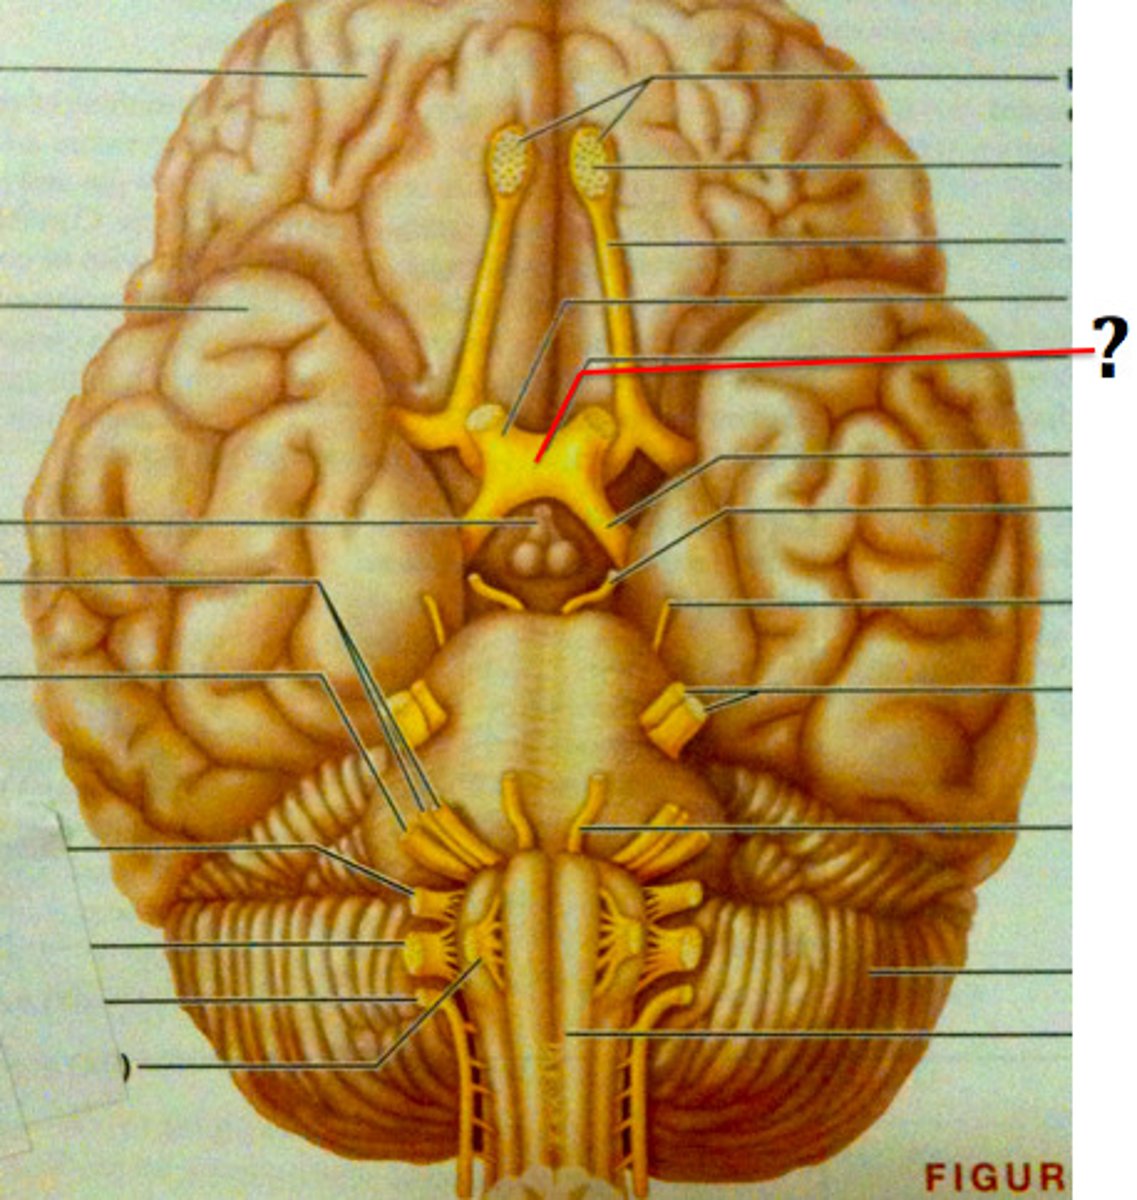

olfactory bulb

olfactory tract

optic chiasma

hypothalamus

thalamus

intermediate mass of thalamus